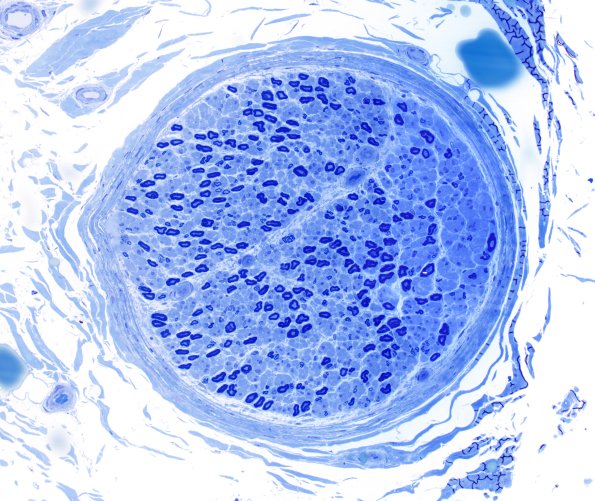

The patient is a 58-year-old female with a history of dysesthesias and bilateral distal leg weakness over the past 5 years who developed complaints of worsening weakness of the left foot over the last six months. EMG/NCS showed mild length dependent polyneuropathy and left S1 radiculopathy. Operative procedure: Sural nerve biopsy and quadriceps muscle biopsy. ---- 26A1,2 There is significant axon loss (small > large). A few large axons show thin myelination for axon caliber, suggestive of a cycle of axonal degeneration and regeneration. There are scattered regenerative clusters, which artificially inflate the apparent number of small myelinated axons.